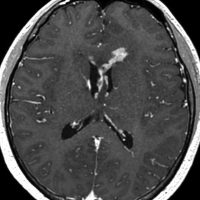

生検後2ヶ月,セカンドオピニオンのために受診された時の画像です。腫瘍が縮小傾向にあります。入院中に行われた何度かのCT被曝の影響で,germinomaの退縮が生じたのだと判断しました。

左はICE化学療法 (IFO/CDDP/VP-16)前,右は1コース終了後です。腫瘍は顕著に縮小してgerminomaとして普通の化学療法反応性を示します。また,松果体と下垂体には腫瘍はありません。